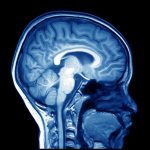

Демиелинизирующее заболевание головного мозга

Демиелинизирующее заболевание представляет собой патологический процесс разрушения миелиновой оболочки, при котором поражаются нейроны головного